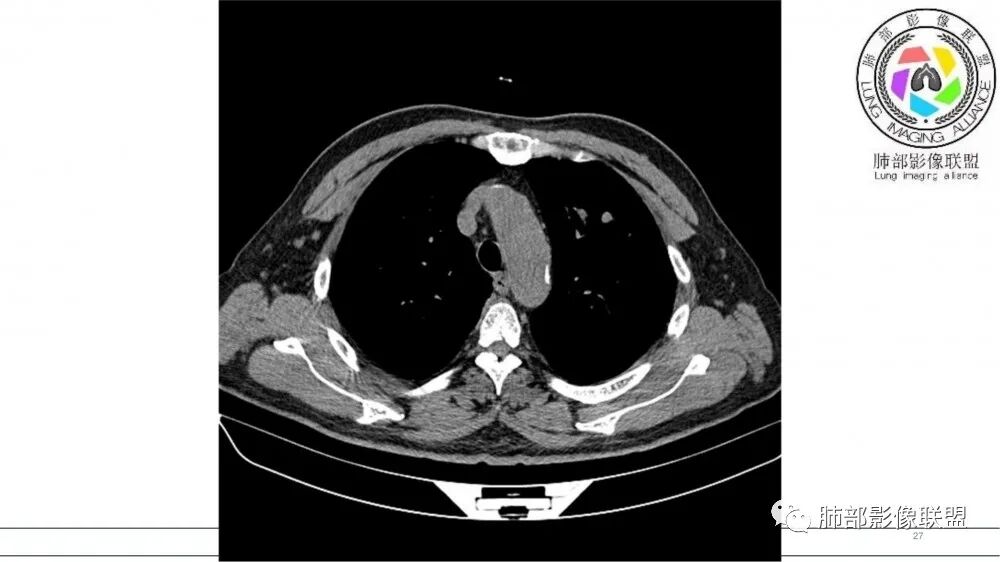

左肺上叶前段支气管内铸形生长软组织影,增强后均匀强化,远侧见斑片状磨玻璃影。考虑恶性病变,粘表?粘液腺?

左肺上叶前段支气管杵状指样扩张,内见实性组织阻塞性,并强化明显,边缘饱满,周边多发小斑点影,小花小草征,老年男性,长期吸烟史,方向恶性,首选支气管内浸润鳞Ca可能性大。

老年男性,肺气肿,吸烟史,左肺上支气管腔内铸型高密度影,呈指套状,远端多发树芽,增强不均匀强化,考虑鳞癌,鉴别小细胞癌

B3指套征,常规不是鳞癌就是ABPA,有强化丶血管造影征,倾向于鳞癌

老年男性,长期吸烟史。左上肺前段沿支气管走形的指套样病变,增强可见病灶强化(排除结核、ABPA(也无气喘症状)),远端多发点状高密度影。考虑恶性肿瘤,鳞癌可能性大。

指套征明确吧

有强化吧,淋巴结大

指套征,扩张支气管内软组织强化,远侧肺野阻塞性炎,纵隔、左肺门肿大淋巴结;老年男性,吸烟,考虑鳞癌,鉴别小

指套征:是影像征象,胸部平片表现为手指状密度增高影,以肺门为中心呈放射状分布,CT显示扩张支气管内低密度黏液栓形成或实性病变,呈管状、树枝状或卵圆形密度增高影;支气管扩张伴近端梗阻时,扩张支气管内部黏液分泌物不能排出而形成。可以伴随远端空气潴留征、阻塞性炎症。

研究报道,中心型 SCLC 经 CT 扫描后通常支气管表现为鼠尾样狭窄,肺门或纵隔肿块明显,由于肿块沿管壁生长表现为顺延支气管形态的不规则形状。病灶相对特征性影像学表现比如鸭蹼状、腊肠状、葫芦状及葡萄状改变,可以出现血管包埋,很少有空洞、空泡,较少引发肺不张,阻塞性炎症成都较轻。与一般肺癌比较,恶性程度高,侵袭力强、病灶很小就容易远处转移!Herzberg 等[19]研究指出,20%以上 SCLC 倍增时间短,预后不良。